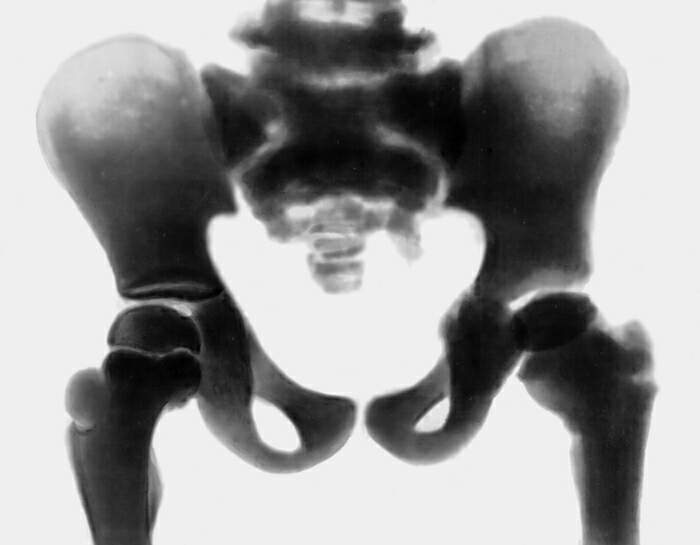

Рентгенограмма костей таза при мраморной болезни

Изменения костей при мраморной болезни